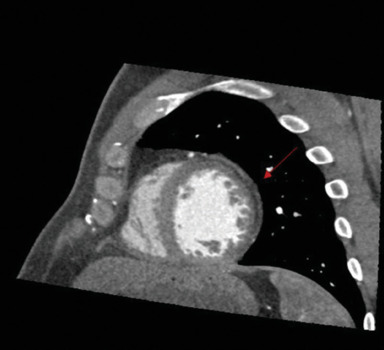

In the evaluation of cardiomyopathies, cardiac computed tomography (CCT) is predominantly used for assessing congenital or acquired coronary artery diseases as a potential etiology underlying the observed myocardial abnormalities. However, its utility is expected to expand. We present a case of an asymptomatic patient with claustrophobia who sought medical attention due to frequent ventricular beats. The resting electrocardiogram revealed repolarization abnormalities characterized by flattened T-waves in the lateral leads and low QRS voltages in the peripheral leads, whereas transthoracic echocardiography was normal. CCT accurately identified hypodense areas indicative of fibrofatty infiltration within the inferolateral and anterior walls of the left ventricle. Furthermore, late iodine contrast-phase imaging revealed subepicardial late enhancement striae in the same regions. These imaging findings were pivotal in establishing a diagnosis of left-dominant arrhythmogenic cardiomyopathy. This clinical vignette underscores the potential of CCT in tissue characterization, particularly when cardiac magnetic resonance imaging is contraindicated or unavailable.

Abstract Image